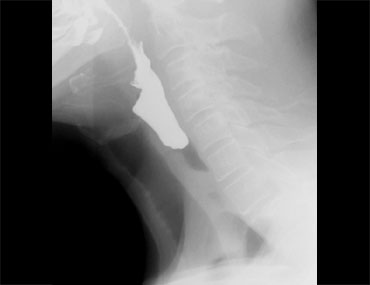

TRÁI: túi thừa nhỏ. GIỮA và PHẢI: túi thừa Zenker thực sự do đóng sớm của cơ nhẫn hầu (mũi tên vàng)

Túi thừa Zenker

Túi thừa Zenker luôn là hậu quả của rối loạn chức năng cơ nhẫn hầu.

Đóng sớm của cơ nhẫn hầu dẫn đến tăng áp lực trong hạ hầu, ngay phía trên cơ nhẫn hầu, khi sóng áp lực của các cơ khít hầu đẩy bolus xuống dưới.

Áp lực tăng này có thể gây phồng ra tại điểm yếu trên thành hầu sau (khe hở Killian).

Ban đầu sẽ tạo thành một túi nhỏ, theo thời gian có thể phát triển và hình thành túi thừa Zenker thực sự (Hình).

Rối loạn chức năng cơ nhẫn hầu

Mở không đủ và đóng sớm là những vấn đề thường gặp nhất của cơ nhẫn hầu.

Bình thường không nên thấy vết lõm của cơ nhẫn hầu trong quá trình bolus đi qua, nhưng đôi khi thấy một vết lõm nhỏ không gây tắc nghẽn và không có ý nghĩa lâm sàng (Hình).

Tuy nhiên, đôi khi điều này có thể giải thích các triệu chứng của bệnh nhân.

Người ta cho rằng sự đi qua của thức ăn kích thích niêm mạc phủ trên cơ nhẫn hầu, gây ra cảm giác vướng họng (globus sensation).